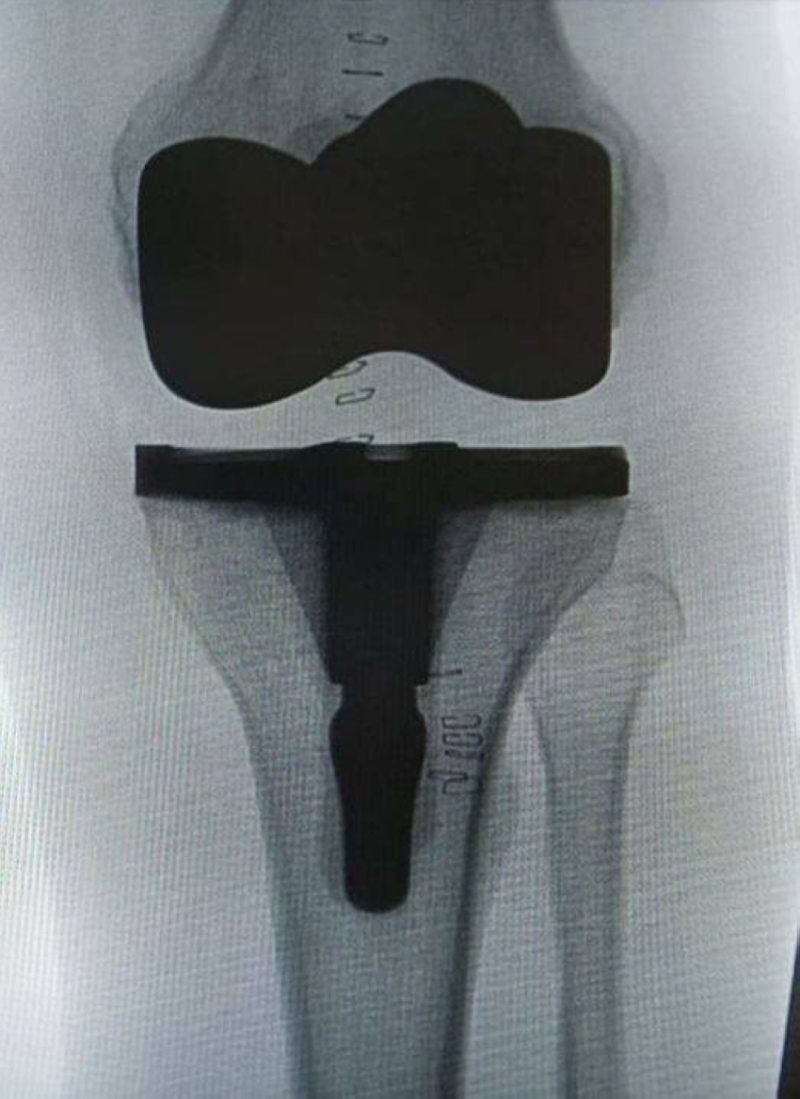

مركز التميز لجراحات المفاصل الصناعية في مستشفى الدرعية عضو تجمع الرياض الصحي الثالث، يواصل تطوير خدماته المتقدمة في استبدال المفاصل، من خلال عمليات دقيقة باستخدام أحدث التقنيات، تسهم في تعزيز جودة الرعاية وتحسين تجربة المرضى.